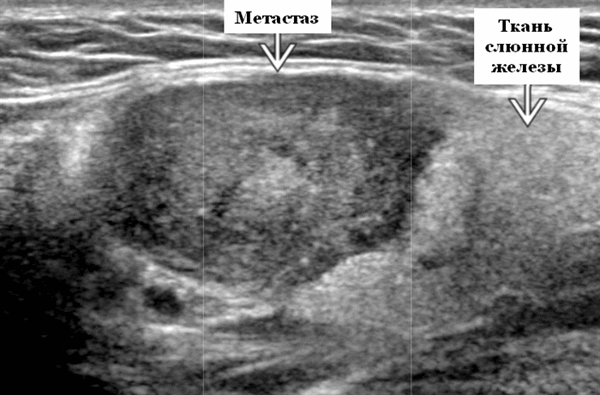

Визуализация. Общие особенности. Само по себе ультразвуковое сканирование метастазов в околоушные лимфоузлы неспецифична. Одиночные или множественные околоушные образования. Хорошо выраженный или плохо выраженный лимфоузел (экстранодальное распространение), однородный или неоднородный с внутренним некрозом. На УЗИ с ЦДК внутриузловая васкуляризация или усиление кровотока. Патология связана с известным первичным раком, часто в прилегающей коже или региональной области головы и шеи. Околоушные и перипаротидные узлы: узловая станция 1-го порядка при плоскоклеточной карциноме кожи (ПКК) и меланоме латеральной части волосистой части головы, ушной раковины / наружного слухового прохода и передней части лица

Морфология. Форма яйцевидная или круглая. Край на УЗИ хорошо выраженный или (при экстранодальном распространении) инфильтративный

Серошкальное УЗИ. Одиночные или множественные гипоэхогенные образования в известном распределении внутрипаротидных лимфоузлов. Хорошо выраженный или слабо окаймленный (экстранодальное распространение). Экстранодальное распространение. Обратите внимание на местную инвазию интрапаротидной наружной сонной артерии (ВСА), ретромандибулярной вены или экстрапаротидных мягких тканей. Аномальная внутренняя архитектура ± эхогенные ворота. Однородный или неоднородный вид с внутренними кистозными участками в некротических узлах ± метастазы в шейные лимфатические узлы